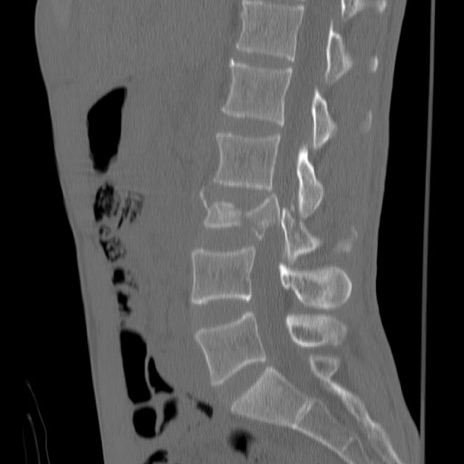

症例3 腰椎CT(矢状断像)

【症例】30歳代男性

【主訴】腰痛

【現病歴】本日旅行先で観光中に、友人と衝突し転倒し受傷。

【身体所見】麻痺なし、右下腿内側前面外側、左下腿内側に知覚鈍麻・しびれ

異常所見と診断は?

腰椎CT